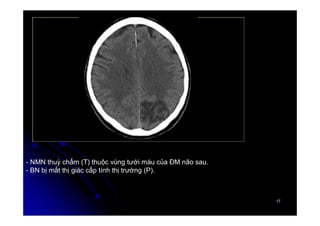

- NMN thuỳ chẩm (T) thuộc vùng tưới máu của ĐM não sau.

- BN bị mất thị giác cấp tính thị trường (P).